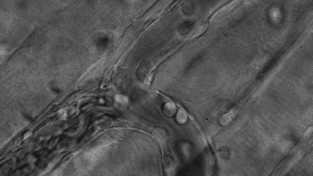

干细胞周围的细胞形成像摇篮样的环境保护着干细胞,这一环境被称为微环境(干细胞巢,niche),它是干细胞存在的基础。微环境由和干细胞相邻的各种细胞、细胞外基质(ECM)以及多种细胞因子等构成。微环境不仅给干细胞提供养分,同时还指导干细胞的行动,决定干细胞的分化方向。

微环境改变是干细胞归巢的始动因素,组织损伤局部表达多种趋化因子、黏附因子、生长因子等各种信号分子。不同的微环境分泌不同的信号分子,吸引干细胞定向到达该组织。干细胞归巢,最终归巢至骨髓,归巢至各个脏器,归巢至炎症及创伤部位。